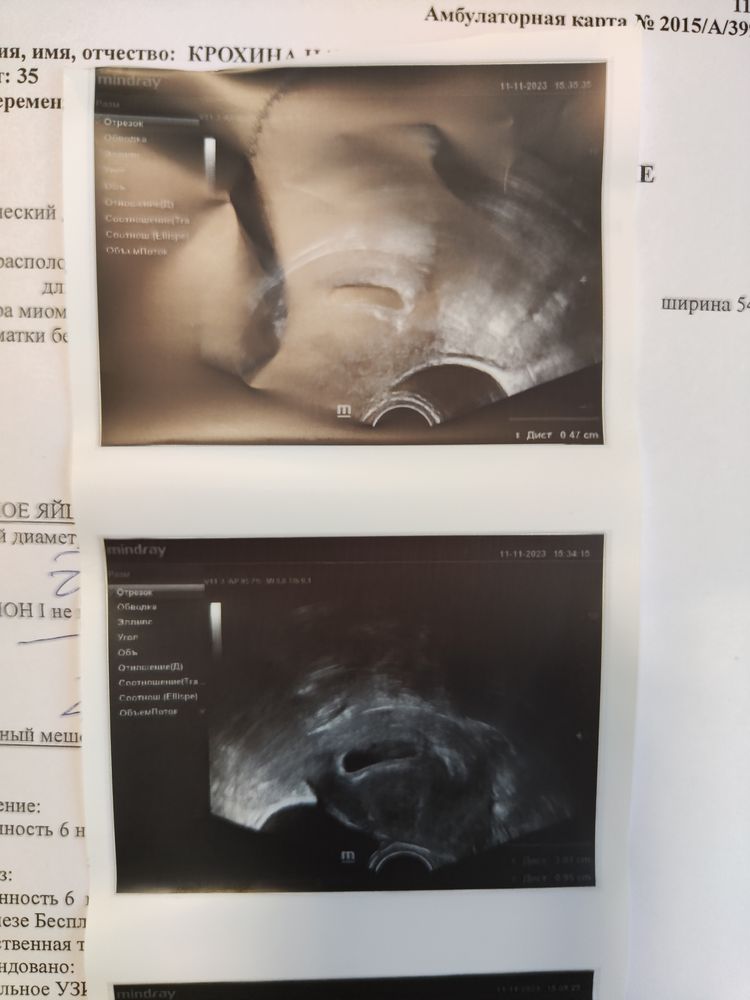

УЗИ в 6 акушерских,анаэмбриония?

Девочки я расстроена( УЗИ сделали пя 21, жм 5мм, эмбрион не нашли( на 14.11 снова УЗИ

У кого было также и эмбрион в итоге нашли? Ещё ставят тонус,яйцо сплюснутое